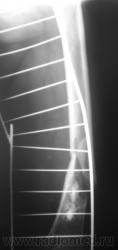

Ну, и, после "репозиции".

После репозиции дистальный отломок смещён латерально на ширину кортикального слоя.

3. Что за включения в мягких тканях по задней поверхности бедра - локальные обызествления в артерии?

3. Включения в мягких тканях, действительно напоминают локальные обызвествления в стенках сосудов.

хочу поддержать доктора Анатолия Шумакова: перелом вряд ли патологический, обызвествление костного мозга бедренной кости и вероятно стенок сосудов

А, вот интересно, такое обызвествление костного мозга, по всей видимости, не могло родиться на "ровном месте"?

По Рейнбергу - чаще посттравматические (травмы без перелома).